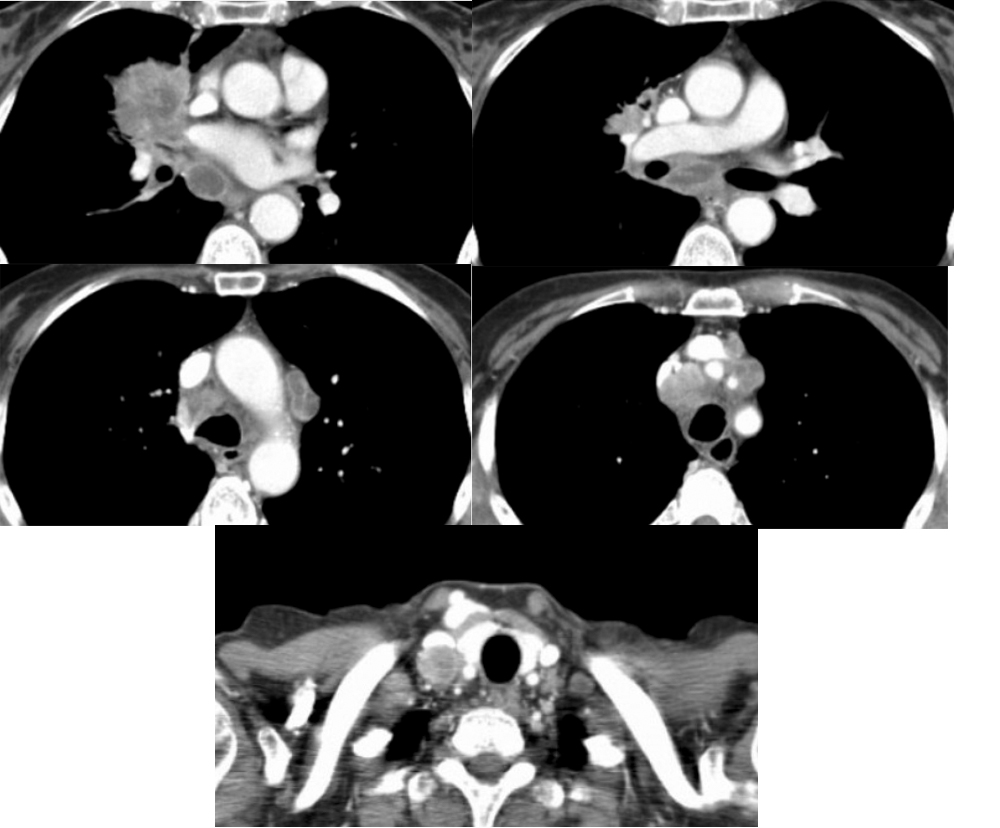

N-стадирование Классификация регионарных лимфатических узлов IASLC 2009 г.

|

|

N-стадия правое легкое

|

N-стадия левое легкое